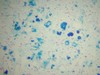

Microglial cell:

- NOT neuroepithelial, derived from monocyte macrophage lineage incorporated into CNS during fetal development

- *Below**:

- Microglial cells form network of CNS antigen presenting cells for immune surveillance

- Activation–> proliferation, migration of microglia

- Most pronounced in viral encephalitis